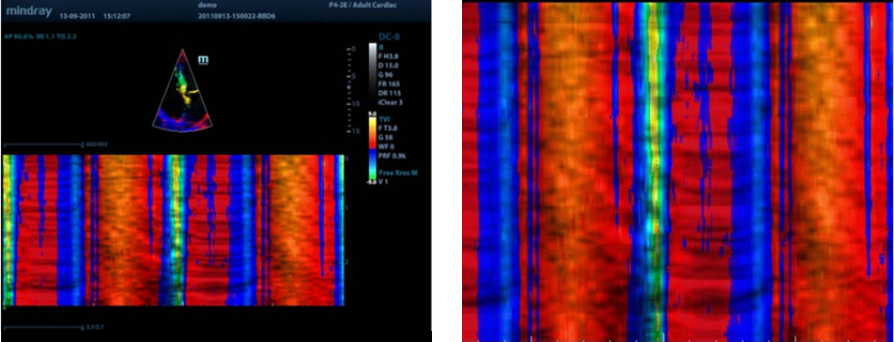

Free Xros CM?

Evaluaci├│n precisa del movimiento en diferentes fases y sincronizaci├│n simult├Īnea del miocardio. Provee alta velocidad de cuadros, proporcionando resultados precisos.

TDI

El diagn├│stico por imagen en modo doppler tisular (TDI) permite evaluar cuantitativamente el movimiento mioc├Īrdico local y su funci├│n, proporcionando as├Ł modos TDI para un diagn├│stico m├Īs r├Īpido y directo.